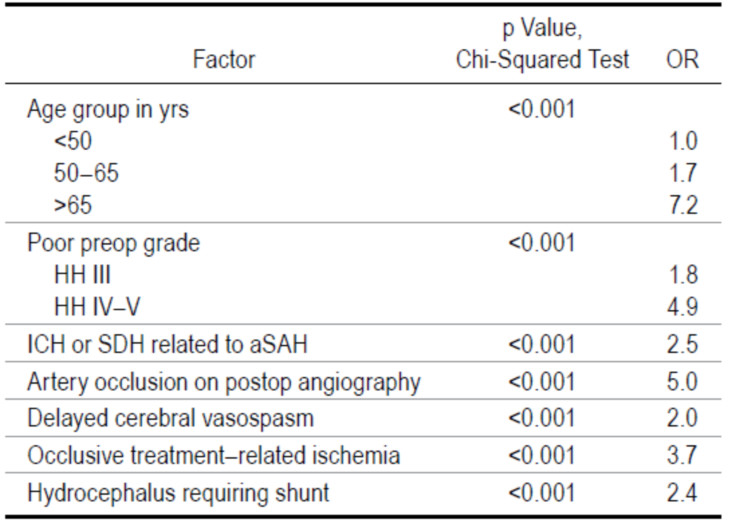

闭塞性治疗后交通动脉 (PCoA) 动脉瘤一直被认为是一个相当简单的过程。本文的目的是确定PCoA动脉瘤破裂和治疗后患者的影像学和临床预后,并评估影响预后的危险因素。在一项回顾性的临床随访研究中,作者收集了1980年至2014年间在同一中心接受过破裂PCoA动脉瘤治疗的连续620名患者的资料。治疗后至少随访1年或直至死亡。

结果发现,在620例患者中,83%采用显微外科夹闭,8%采用血管内栓塞治疗,2%采用联合治疗,1%采用间接手术方法,6%采用保守方法。最常见的手术并发症是与治疗相关的脑梗死(15%)。动脉栓塞的发生率高于预期(显微外科组10%,血管内治疗组8%)。动脉瘤性蛛网膜下腔出血1年后,多数患者恢复良好(改良Rankin量表[mRS]评分0-2分:386例[62%])。严重残疾的患者比例相当小(mRS评分4-5分:27例[4%])。20%的患者在发病第一年内死亡。根据多变量分析,导致不良预后的独立危险因素包括:术前临床条件差、动脉瘤破裂导致的脑内或硬膜下血肿、年龄超过65岁、术后血管造影发现动脉闭塞、与闭塞治疗相关的缺血、迟发性脑血管痉挛和需要行分流术的脑积水。

因此,作者认为尽管大多数患者在PCoA动脉瘤破裂和治疗后的第一年恢复良好,但闭塞性治疗相关并发症的发生率仍高于预期,而且在最初分级良好的患者中也有一定的发病率。即使在体量大的神经血管病中心,闭塞性治疗破裂的PCoA动脉瘤似乎也是一个高风险的过程。

图:闭塞性治疗破裂后交通动脉瘤1年后患者出现不良预后(mRS评分>2)的独立危险因素。